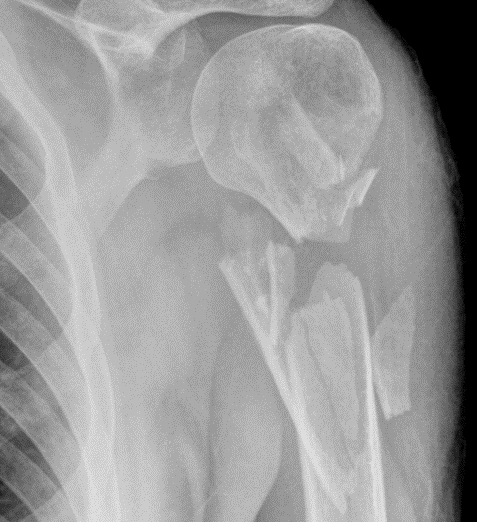

What type of fracture is this?

Comminuted/Multi fragmental

Must have >3 pieces